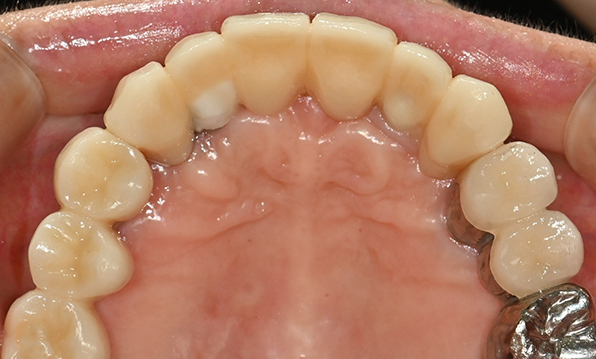

잇몸뼈가 얇은 상태

-

잇몸뼈 충분히 이식 후 임플란트 식립

성공을 위한 노하우, 잇몸뼈 재건 기술

전체 임플란트를 해야하는 환자들은

대부분 고령의 환자들로 오랜 틀니 사용

또는 노화로 인해 치조골이

거의 남아있지 않는 경우가 많습니다.

이 때, 치조골 이식을 병행하여 잇몸뼈 재건 후 안정적인 임플란트 식립을 하고 있습니다.

치료기간 : 2021.04.12~2021.09.15